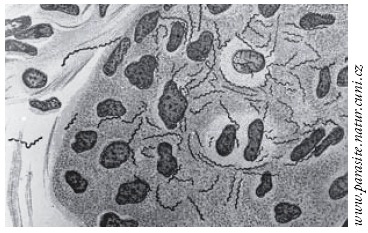

Treponema pallidum

Treponema pallidum

Treponema pallidum merupakan salah satu bakteri anggota filum Spirochaetae. Bakteri ini berbentuk spiral. Terdapat empat subspesies yang sudah ditemukan, yaitu …

Treponema pallidum merupakan salah satu bakteri anggota filum Spirochaetae. Bakteri ini berbentuk spiral. Terdapat empat subspesies yang sudah ditemukan, yaitu …